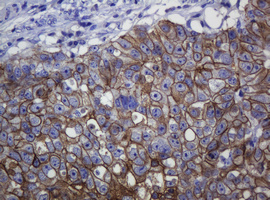

Immunohistochemical staining of paraffin-embedded Human liver tissue within the normal limits using anti-CDH1 mouse monoclonal antibody. (Heat-induced epitope retrieval by 10mM citric buffer, pH6.0, 120°C for 3min, M00063-5)